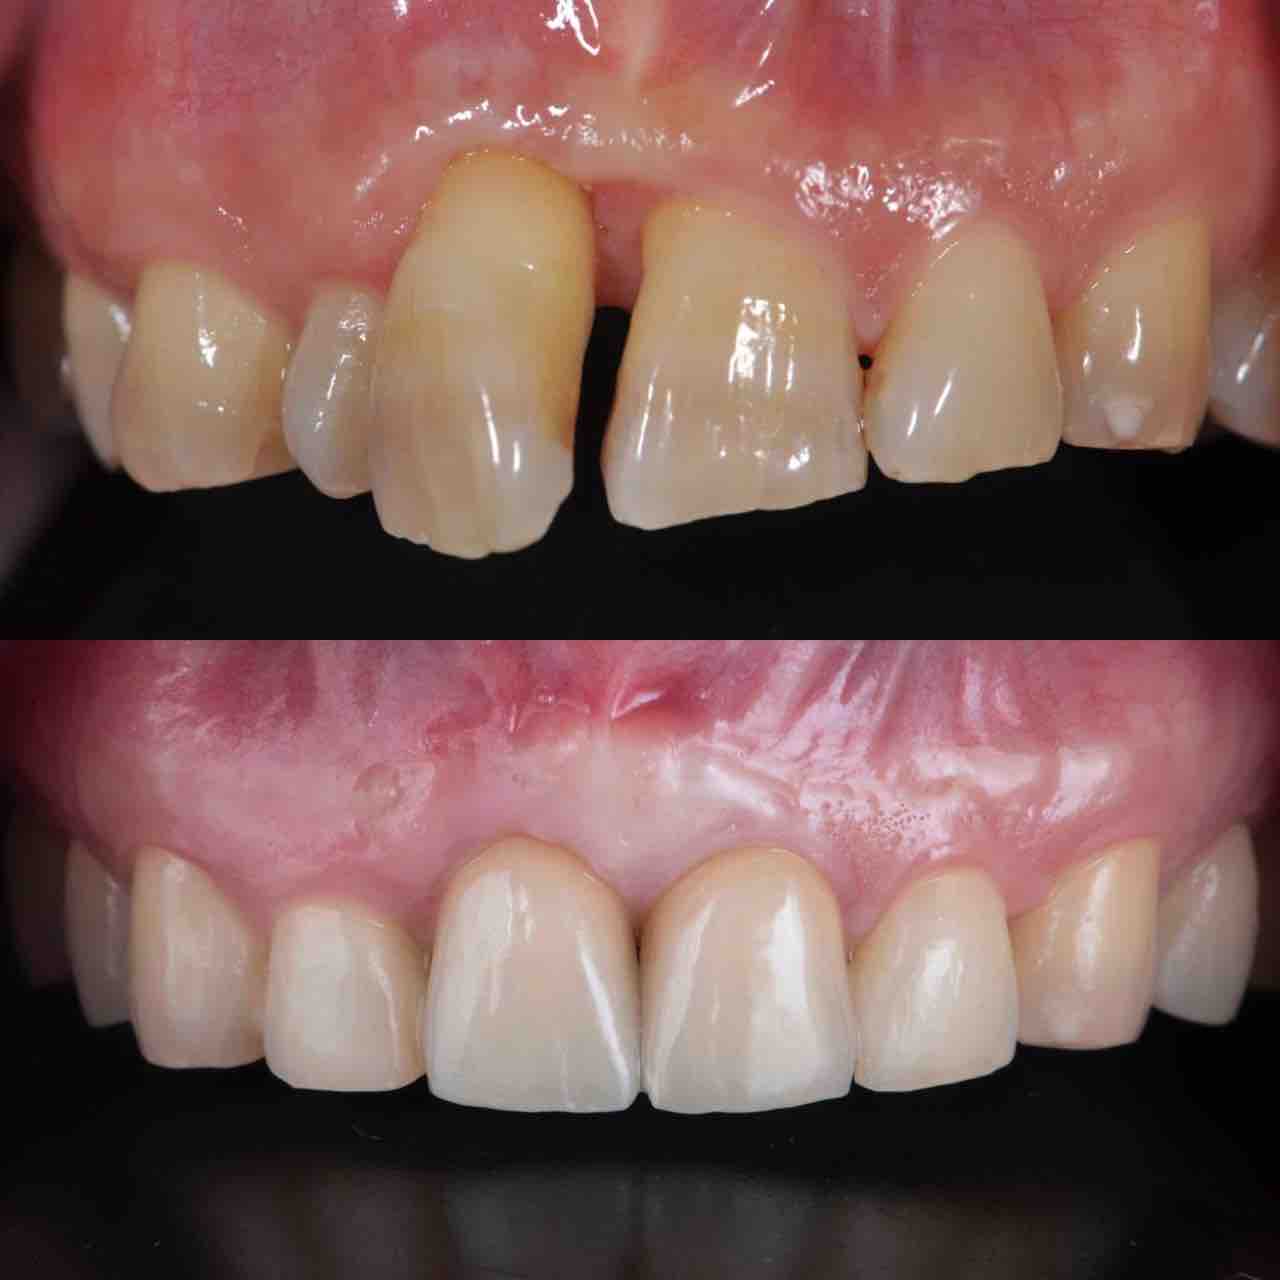

¥¤¥ó¥¹¥¿¥°¥é¥à¤ËºÜ¤»¤Æ¤¤¤ëÅö±¡¤Î¾ÉÎã¤Ç¤¹

ðÌî»õ²Ê¾ÉÎ㢠ÀèÅ··ç»¶ºÀµ¥¤¥ó¥×¥é¥ó¥È

ðÌî»õ²Ê¾ÉÎã¡¶ºÀµ¥¤¥ó¥×¥é¥ó¥È¥»¥é¥ß¥Ã¥¯